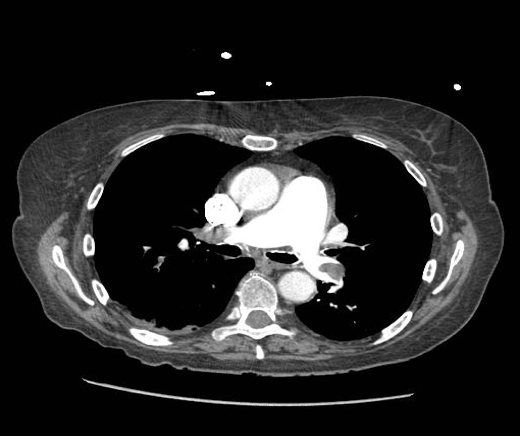

What is this CTPA showing?

Pulmonary embolism. Areas of radiolucency are the PE